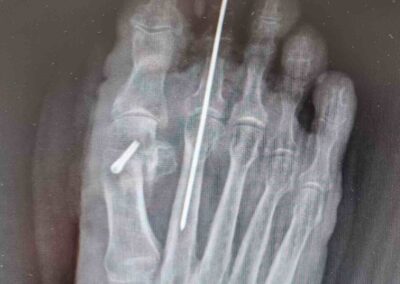

Le tecniche chirurgiche a nostra disposizione sono molteplici e vanno individualizzate sul paziente. Tra le varie preferisco la osteotomia distale del primo metatarso fissata con adeguati mezzi di sintesi preferibilmente in titanio associata al rilascio della capsula sul versante laterale. In alcuni casi difficili può essere indicato associare anche una osteotomia della prima falange dell’alluce oltre a trattamenti diretti alla correzione di eventuali griffe digitali associate.

Non posiziono fili metallici e quando tratto isolatamente la griffe digitale opero in anestesia locale e ambulatorialmente concedendo immediatamente il carico libero senza protezione alcuna. Il postoperatorio dell’intervento correttivo per alluce valgo prevede invece l’uso di una scarpa con suola piatta e rigida per scarico sull’avampiede da tenere in media cinque settimane durante le quali il paziente autonomamente provvederà alla mobilizzazione attiva e autoassistita di tutti i distretti articolari del piede operato (evito assolutamente di operare in contemporanea i due piedi).

In merito poi alla tecnica MININVASIVA personalmente preferisco usarla nelle osteotomie dei raggi digitali escluso il primo.